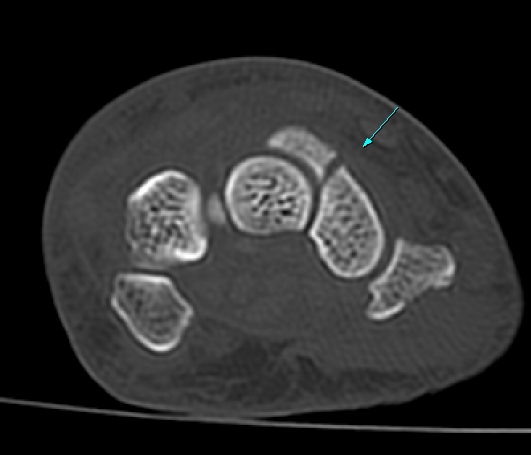

CT °Ë»ç

È®ÁøÀ» À§ÇÑ ÃÊÀ½ÆÄ°Ë»ç¿¡¼ ÁÖ»ó°ñ °ñÀý È®ÀÓ µÊ.